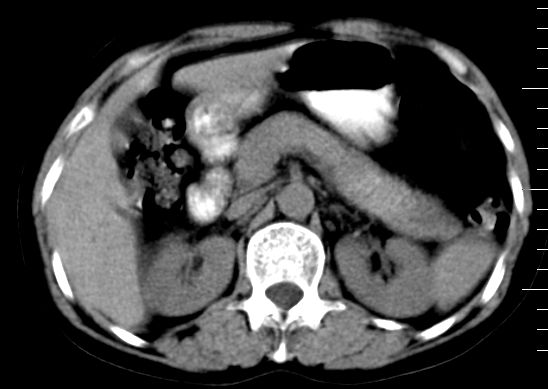

标题: CT10752:F,52岁,反复上腹部疼痛,平扫+增强. [打印本页]

f、52岁,反复上腹部疼痛2年。肺结核病史10多年,胸片双上肺结核纤维化。

ct表现:

肝大小形态未见异常,肝内外胆管无扩张,肝s8段见一动脉期明显血管样强化结节,门脉期呈高密度,延迟期呈等密度,胆囊不大,增强扫描见胆囊及胆囊颈管壁增厚,有强化。

双肾灌注良好,代谢增快,动脉期肾盂见造影剂,左肾下极背侧见一略低密度病灶,延迟期见似不强化囊肿,双侧肾上腺未见异常。

胰腺及脾未见异常。肾门水平腹膜后见小淋巴结。腹腔未见积液征象。

诊断:

1、胆囊炎(轻度)。

2、肝s8段结节,考虑小血管瘤。

3、左肾下极低密度灶,考虑囊肿可能性大,建议随访,除外小肾癌(无强化可以基本除外)。

4、目前ct表现尚不能解释患者上腹部疼痛,建议上消造影检查,除外胃炎等疾患。